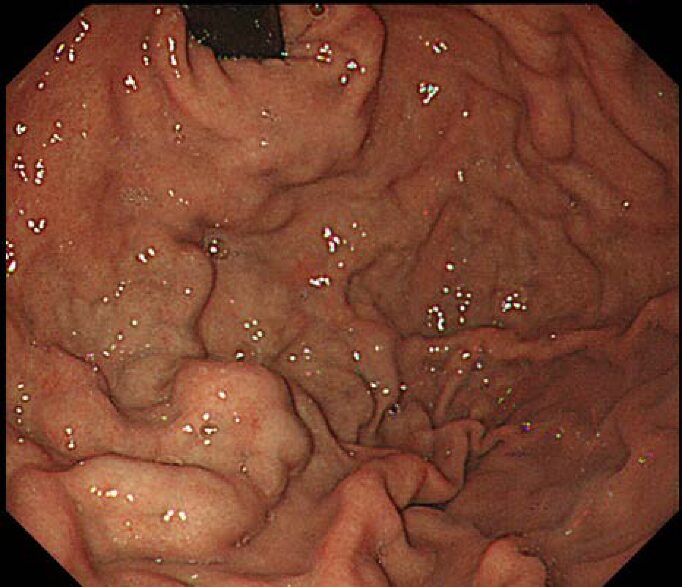

胃底腺ポリープは周囲の胃粘膜と同じ色調、模様をしている2-3mm大の小さなポリープで、胃穹窿部から胃体部、特に大弯側に複数みられることを特徴としています。ヘリコバクター・ピロリ陰性のきれいな胃にしか発生しないことから、胃底腺ポリープが認められた胃は、胃がんのリスクが低いと考えられます。

ヘリコバクター・ピロリ菌陰性者が増加しており、胃内鏡検査で偶然発見される機会も増加しています。

女性に多くみられ、女性ホルモンなどの関与の指摘もされていますが、はっきりした原因は不明です。胃食道逆流症(GERD)などでプロトンポンプ阻害薬を長期間服用するとポリープが増大し数が増加すると考えられています。ほとんどの方は経過観察していくとポリープの数は増えていく事が多くみられます。

胃底腺ポリープは、ヘリコバクター・ピロリ陰性で胃粘膜の萎縮が少ない胃酸分泌が盛んな胃粘膜に多く発生します。そのため胃酸過多症状(上腹部痛、胸やけなど)を自覚することがありますが、胃底腺ポリープそのものの症状ではありません。

胃底腺ポリープは基本的に経過観察で問題ありません。ほとんどの胃底腺ポリープは内視鏡治療を含めた切除の必要はありません。

胃底腺ポリープの中で、徐々に大きくなる場合、赤みが強くなる場合に、ごく稀に胃底腺型胃がんを生じることがあるので、胃底腺ポリープは100%安心というわけではありません。